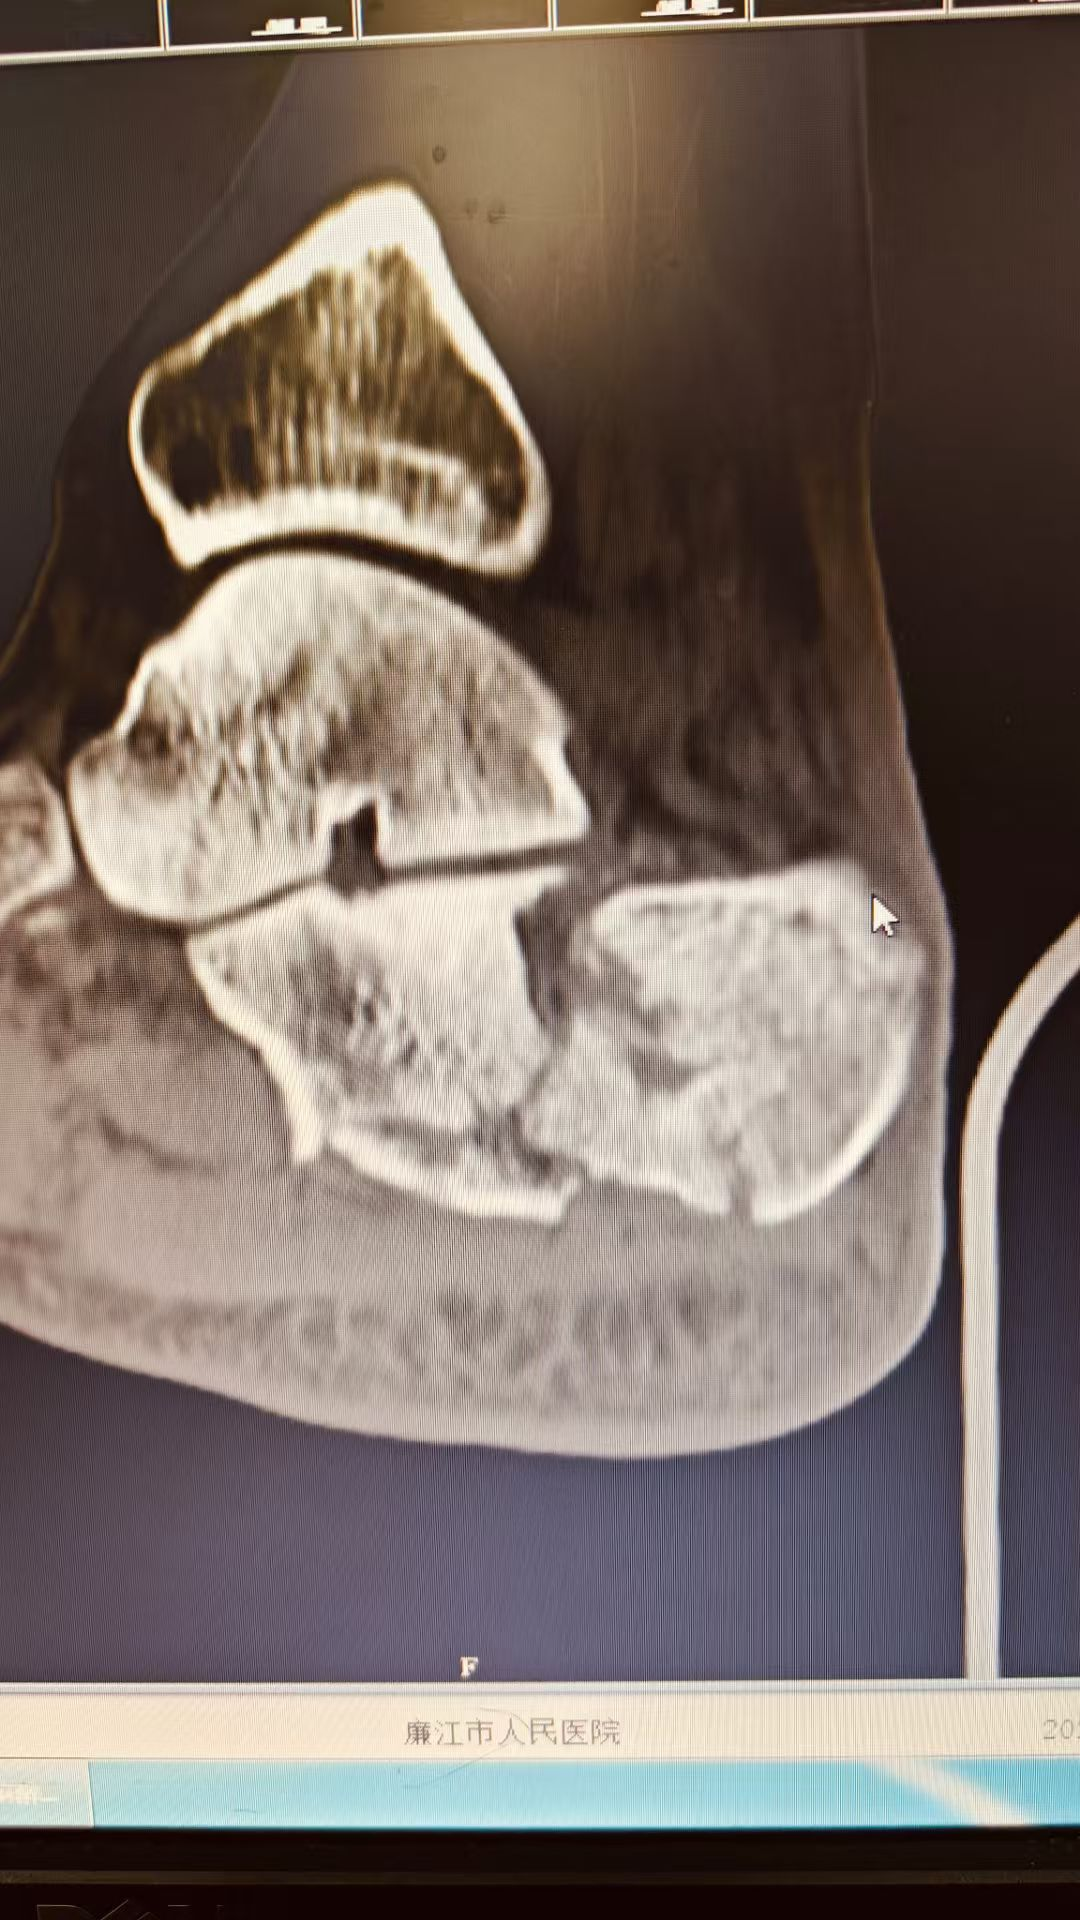

图片图片图片

跟骨粉碎性骨折闭合复位微创经皮穿针内固定